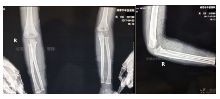

入院拍片如下:

患者性别:男

患者年龄:4岁

简要病史:跌倒致右肘部畸形、肿痛、活动受限,就诊于我院,拍片诊断为肱骨髁上骨折。

治疗经过:入院行四步复位法手法整复,小夹板外固定